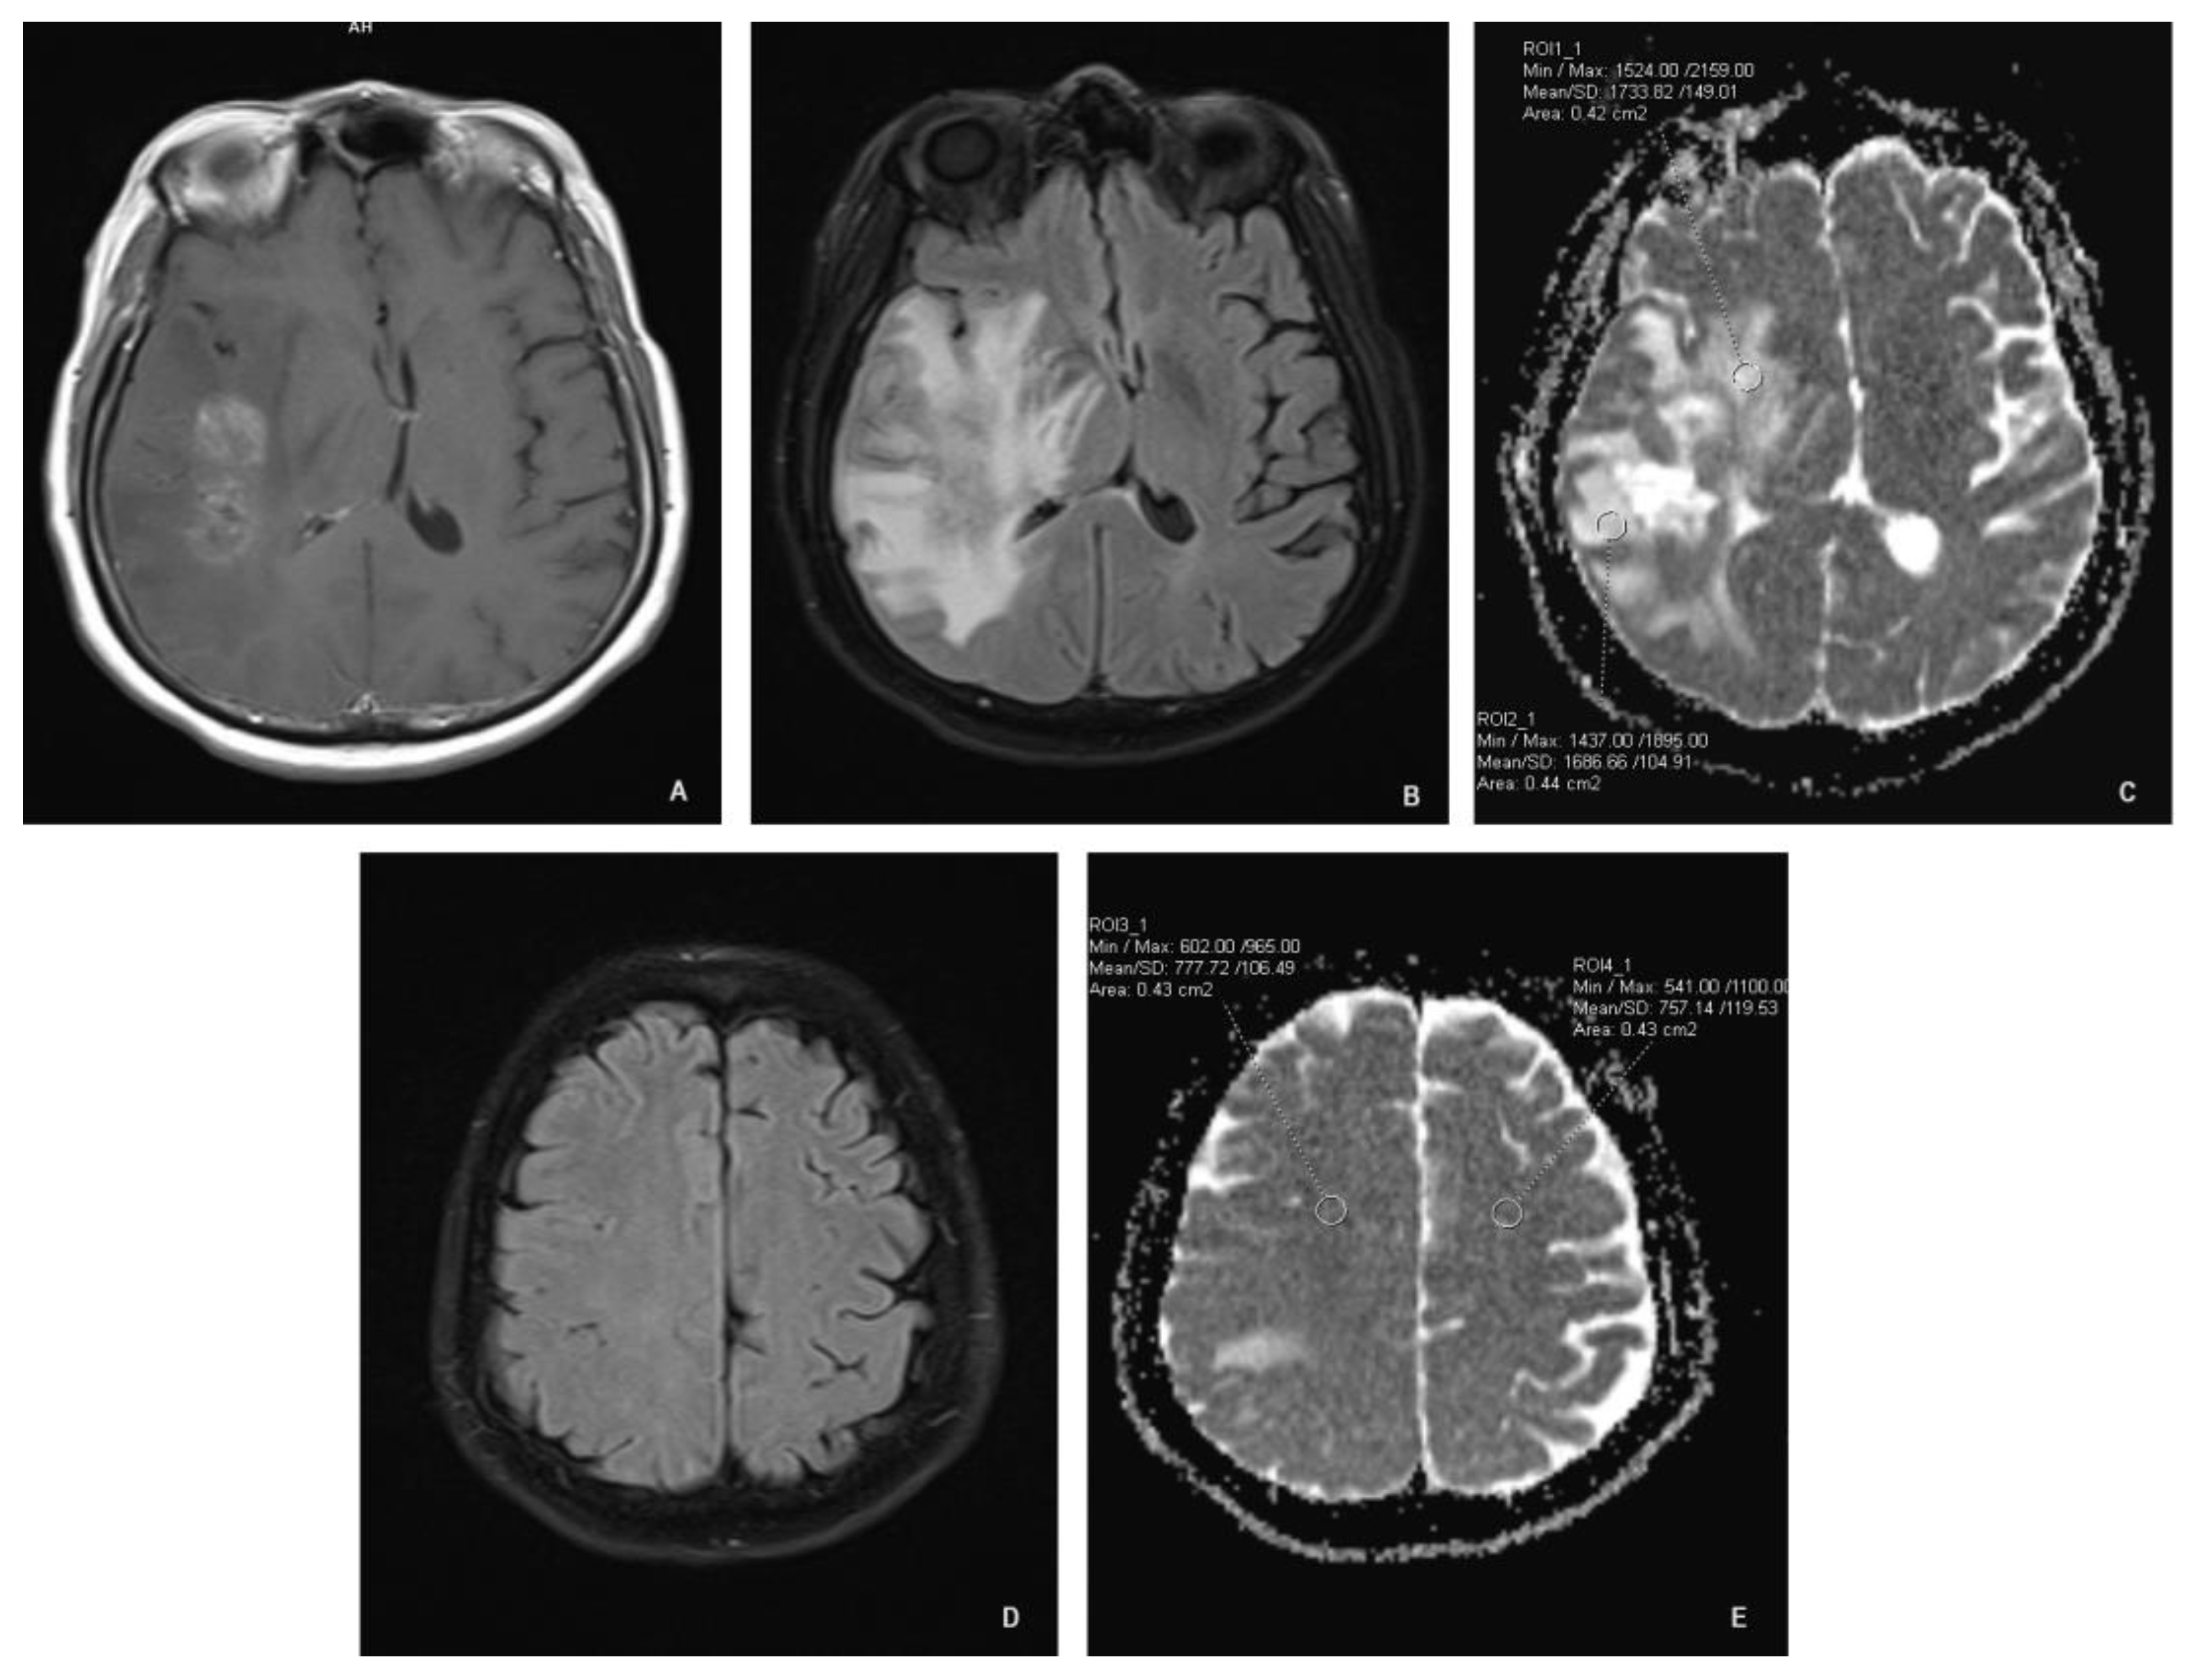

All scans were analyzed with the software provided by the scanner manufacturer (Syngo.via; Siemens; Munich, Germany). Each MRI study was evaluated by a radiologist. Using freehand volume of interest tool we outlined the margins of the enhancing lesion. Two region of interest (ROI) circles were placed adjacent to the enhancing area (approximately 2 mm away from the enhancing margin, within the signal abnormality on FLAIR images), one ROI at least 4 cm away from the enhancement in the ipsilateral normal appearing white matter (NAWM), and an additional ROI in the contralateral NAWM in a symmetric fashion (Figure 1). The surface area of ROI circles was 0,4-0,5 cm2 (Figure 1.). The software calculated mean ADC values of the selected ROIs.

A: T1 axial spin-echo showing the enhancing lesion; B: Axial FLAIR showing white matter hyperintensity adjacent to the enhancing lesion; C: Axial ADC map showing ROI placement adjacent to the enhancing lesion; D: Axial FLAIR showing normal appearing white matter; E: Axial ADC at the same level as “D” showing ROI placement.

Figure 1. ROI placement.